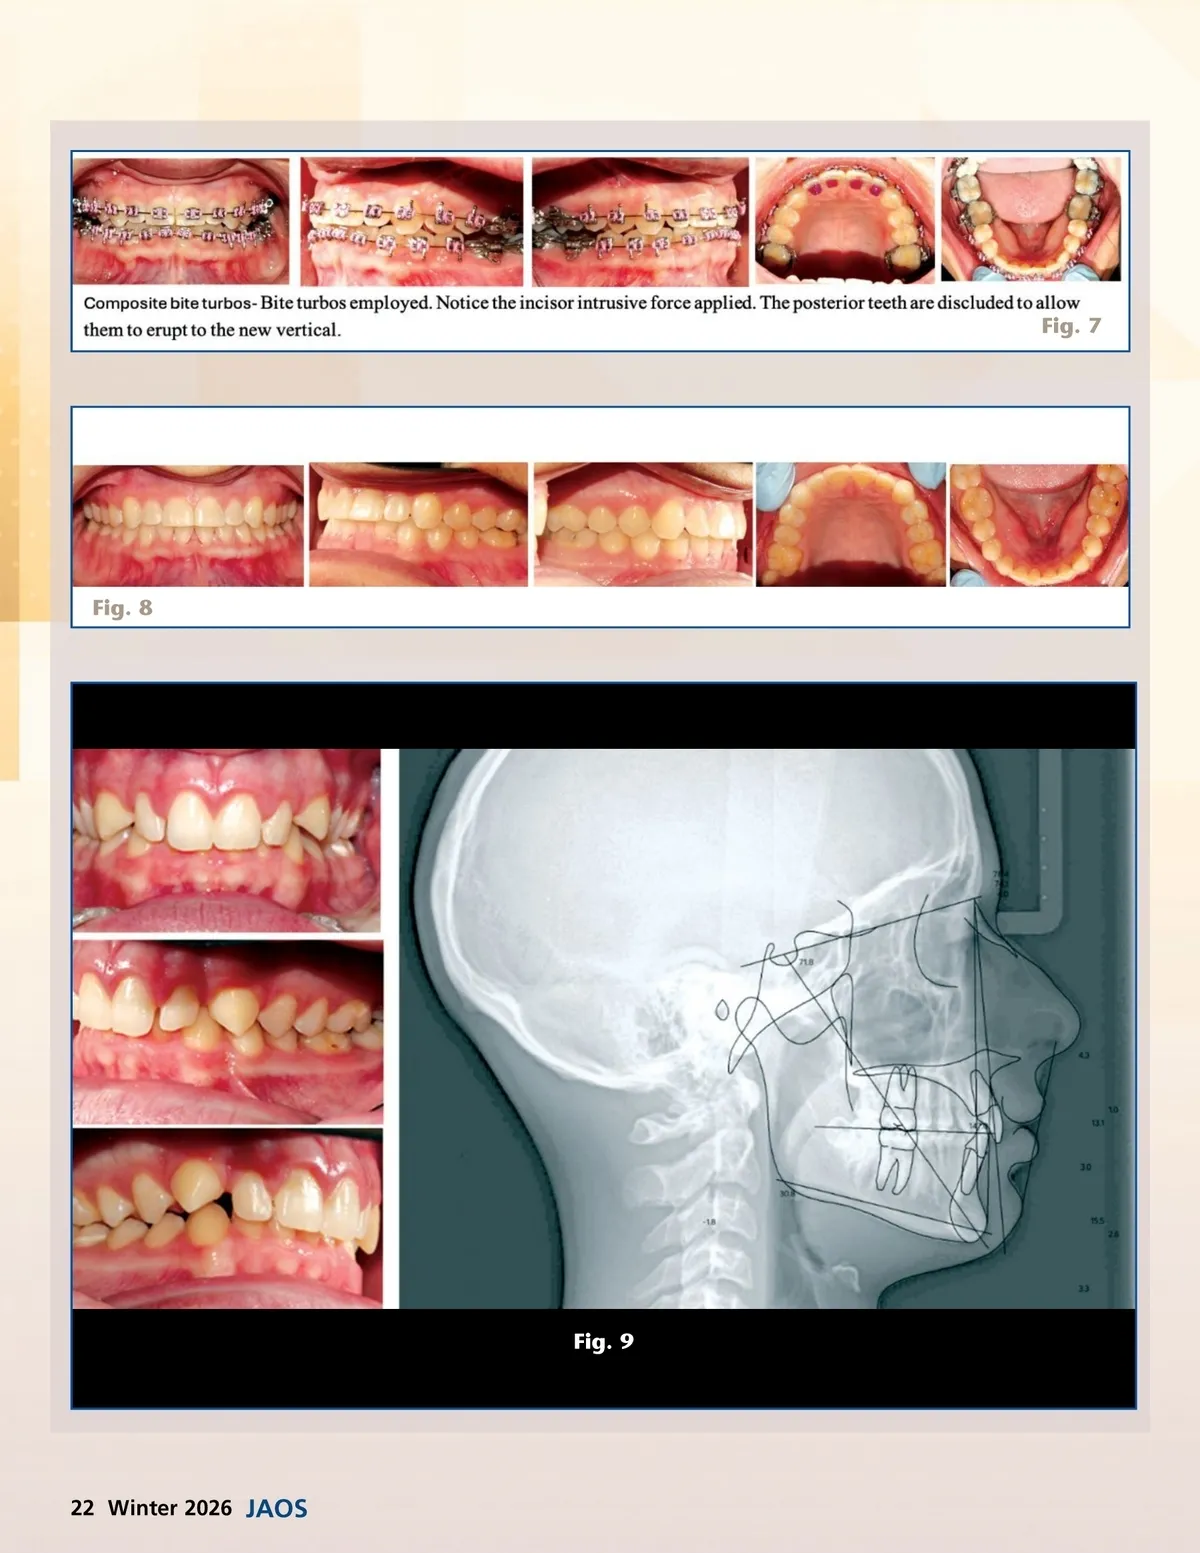

Fig. 7 Fig. 8 Fig. 9 22 Winter 2026 JAOS